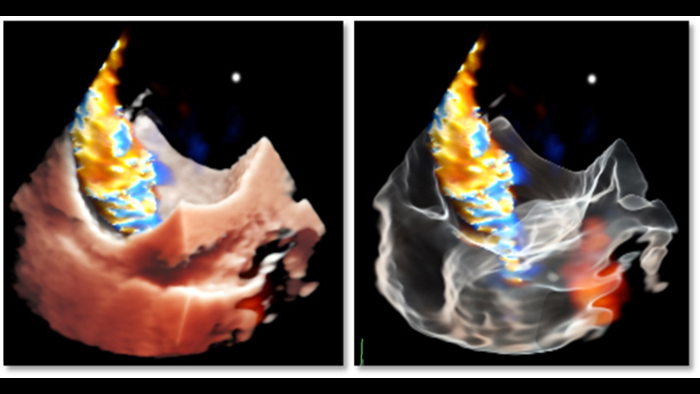

Deep insights with TrueVue color and GlassVue

Cardiac TrueVue photorealistic rendering with MultiVue image alignment